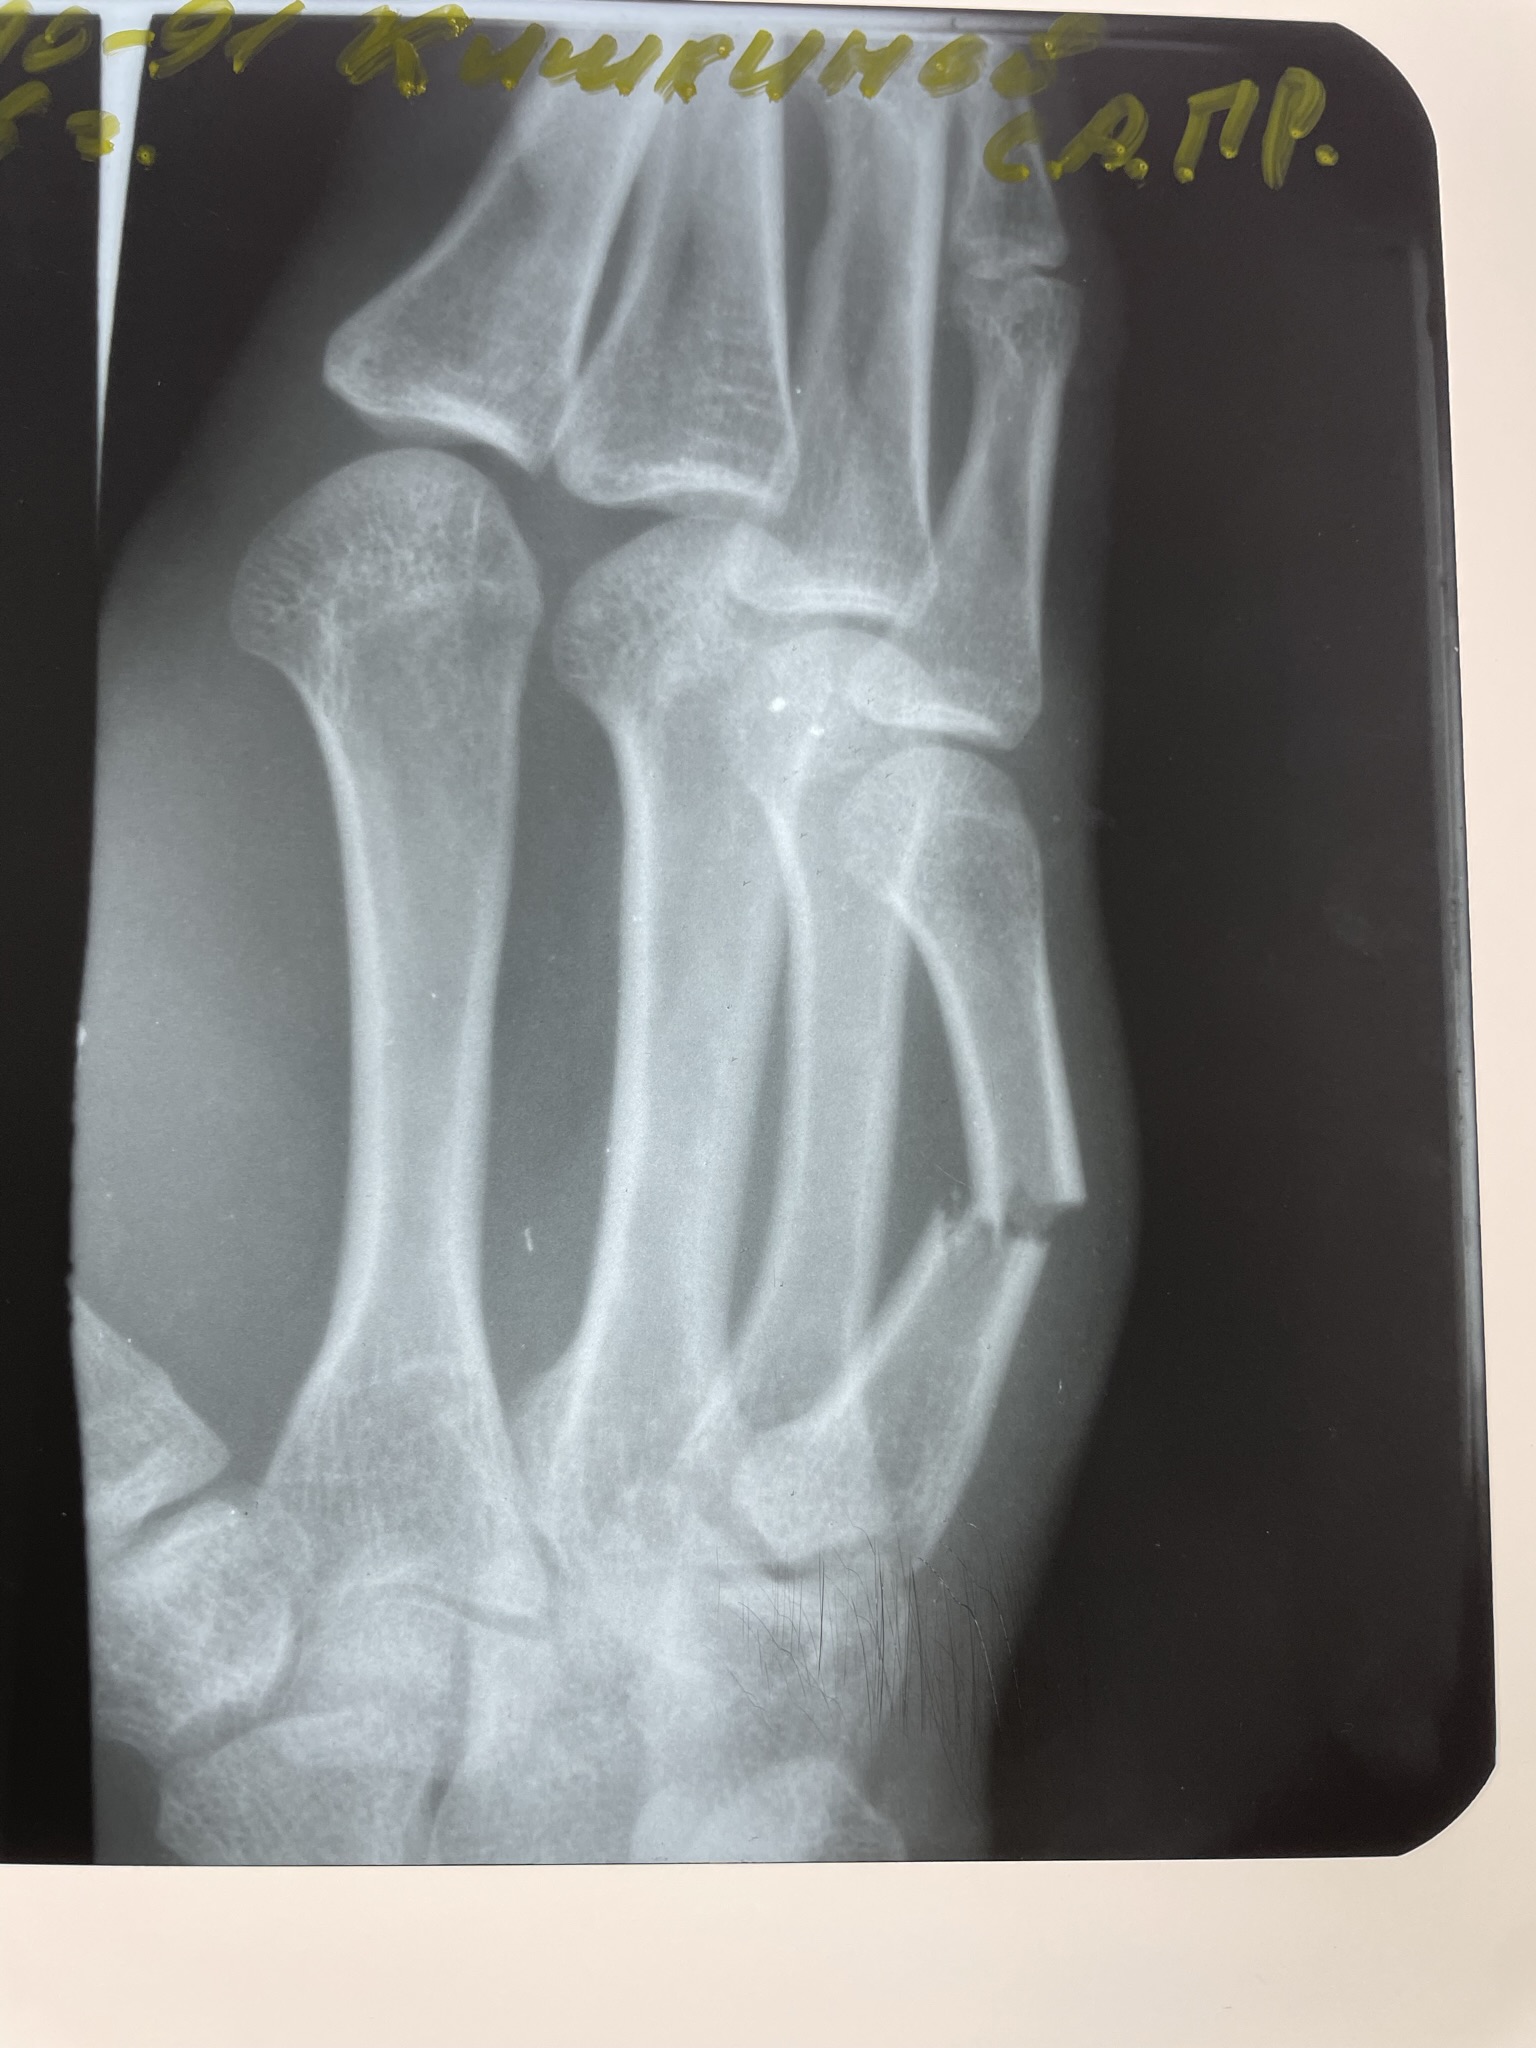

Переломы пястных костей диагностируются с клинического осмотра, во время которого врач оценивает симптомы и проводит физикальное обследование. Основным методом диагностики является рентгенография, которая позволяет визуализировать состояние костей и выявить наличие перелома. В некоторых случаях может потребоваться компьютерная томография (КТ) для более детального изучения повреждений, особенно если есть подозрение на сложные или нестандартные переломы.

Клинический случай: остеосинтез перелома 2 пястной кости — до операции

Пациент с нестабильным переломом 2 пястной кости. Документируем боль, отёк и ограничения движений перед оперативным лечением.

Клинический случай: остеосинтез перелома 2 пястной кости — во время операции

Выполнена репозиция и фиксация пластиночной системой. Фото демонстрируют этапы доступа и установки пластины.